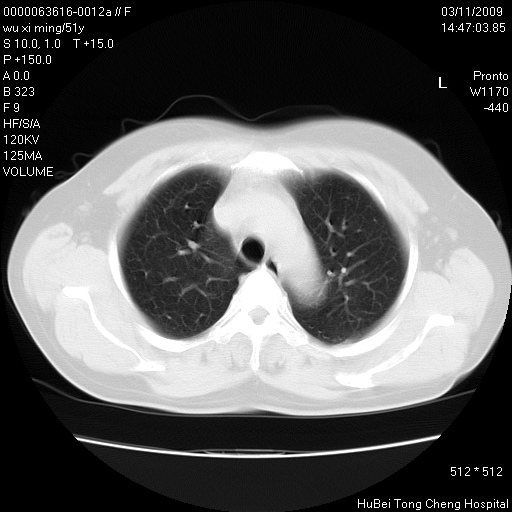

患者 女,51岁。因“胆囊炎,胆囊结石”,行常规术前胸部x线检查发现:右上肺结节病灶,建议行进一步检查。患者无咳嗽、咳痰及咯血等呼吸道症状,近期出现背部疼痛不适。

胸部ct轴位平扫(层厚10mm,螺距1.5,重建间隔10mm;部分层面:层厚3mm,螺距1.0,重建间隔3mm),图像如下: